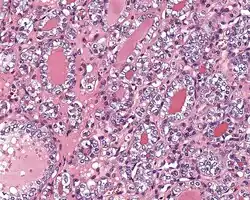

1) Encapsulated or partially encapsulated. The tumors are usually very well delimited or circumscribed, with the majority encapsulated, surrounded by a well formed fibrous connective tissue capsule.

2) Complete absence of invasion of any kind in a tumor that has been thoroughly and carefully evaluated with the whole capsule of the lesion sampled.

3) Predominantly follicular pattern of growth. Papillary structures should not be present. Further, solid, insular, or trabecular architecture must be <30% of the overall tumor for this category to still apply. Colloid (the material that thyroid follicular cells create) is easily identified throughout.